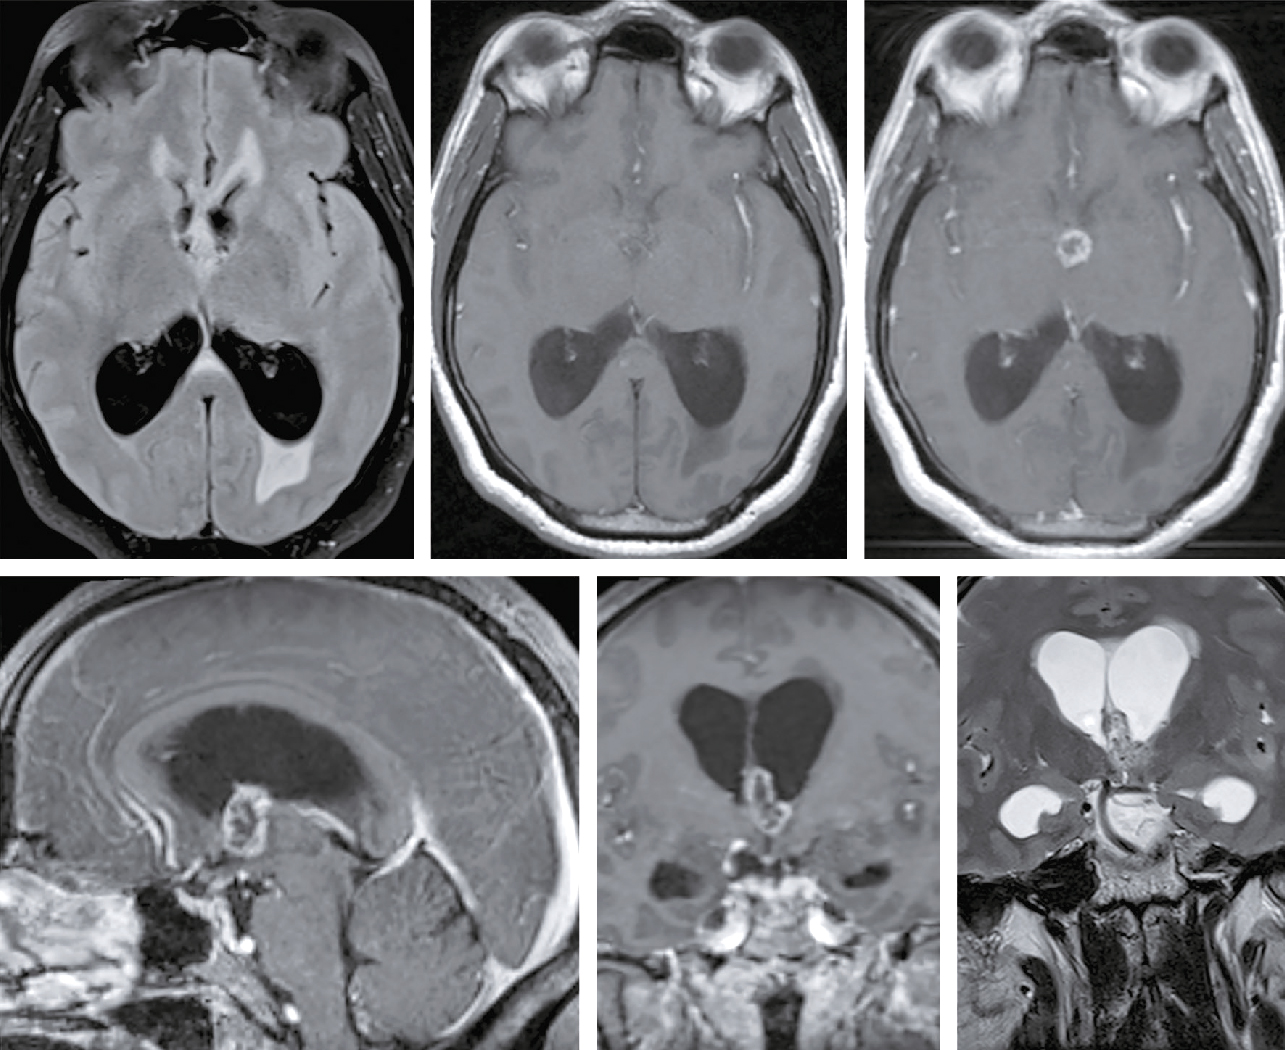

Une IRM encéphalique est réalisée (fig. 31.7). Sur cette planche, quels sont les éléments évocateurs du diagnostic de sclérose en plaques (SEP) ?

L'image montre trois coupes transversales d'un cerveau humain prises par imagerie par résonance magnétique (IRM). Chaque coupe est étiquetée avec des informations spécifiques : "FH 14 head", "FH 20 head" et "FH 26 head". Ces étiquettes indiquent probablement différentes sections ou niveaux de la tête. Les images montrent des zones de signal hyperintense, qui apparaissent comme des taches blanches sur les images. Ces zones peuvent indiquer des anomalies telles que des lésions, des plaques ou d'autres types de pathologies cérébrales. Les coupes transversales permettent de visualiser différentes parties du cerveau, y compris les ventricules cérébraux et la matière blanche environnante. Les images sont intéressantes car elles permettent de détecter et de surveiller des conditions neurologiques, d'évaluer l'étendue des dommages et de planifier des traitements appropriés. Les variations dans les images peuvent fournir des informations cruciales sur la progression de la maladie ou l'efficacité des interventions thérapeutiques.

- A 585présence d’hypersignaux de la substance blanche

- B localisation surtout périventriculaire des hypersignaux

- C aspect arrondi des hypersignaux

- D présence de trous noirs

- E atrophie cérébrale marquée

Devant cette atteinte du nerf III avec douleurs associées, vous souhaitez éliminer la présence d’un anévrisme carotidien, raison pour laquelle vous décidez de réaliser une IRM cérébrale avec ARM cervicale. Il n’y a pas d’anévrisme mais d’autres images attirent votre attention. Quelles sont les coupes et séquences utilisées pour ces deux images (fig. 31.12 et 31.13) ?

L'image montre une coupe transversale d'un cerveau humain obtenue par imagerie par résonance magnétique (IRM). Cette image est en niveaux de gris et présente des structures cérébrales distinctes. On peut observer les hémisphères cérébraux, séparés par la fissure interhémisphérique. Les zones plus claires sur l'image représentent des anomalies ou des lésions, qui peuvent être dues à diverses conditions médicales telles que la sclérose en plaques, les tumeurs, ou les accidents vasculaires cérébraux. Les zones sombres au centre de l'image correspondent aux ventricules cérébraux, qui contiennent le liquide céphalorachidien. Cette image est intéressante car elle permet aux professionnels de la santé de diagnostiquer et de surveiller les maladies neurologiques en visualisant les structures internes du cerveau et en identifiant les anomalies. Les détails observables, comme la localisation et la taille des lésions, sont cruciaux pour une évaluation approfondie. Ce type d'imagerie aide à comprendre l'étendue des dommages et à planifier des traitements appropriés. En analysant ces images, les médecins peuvent mieux comprendre la santé cérébrale et prendre des décisions éclairées concernant les soins à apporter au patient.

L'image montre une coupe transversale d'un cerveau humain obtenue par imagerie par résonance magnétique (IRM). Cette image en niveaux de gris présente les structures internes du cerveau, y compris les circonvolutions et les sillons. Les variations de teintes indiquent différentes densités de tissus et de liquides. Les zones plus claires peuvent correspondre à des anomalies ou des lésions, telles que des tumeurs, des plaques ou des signes de maladies neurologiques. Les zones sombres au centre de l'image représentent les ventricules cérébraux, remplis de liquide céphalorachidien. Cette image est utilisée pour diagnostiquer et surveiller diverses pathologies cérébrales, fournissant des informations cruciales pour les professionnels de la santé. L'IRM est une technique non invasive qui permet de visualiser avec précision les détails anatomiques du cerveau sans utiliser de rayonnement ionisant. Grâce à cette image, les médecins peuvent identifier des anomalies, évaluer leur étendue et planifier les traitements nécessaires pour les patients atteints de troubles neurologiques. Les coupes transversales du cerveau montrent également les principales régions cérébrales, permettant une meilleure compréhension de la structure et des fonctions du cerveau humain.

593

-

- A coupes axiales en séquence T2 injectées

- B coupes axiales en séquence T1 non injectées

- C coupes sagittales en séquence T2/FLAIR

- D coupes axiales en séquence T2/FLAIR

- E coupes axiales en séquence 3D TOF

Question 8 – QRM

Les lésions multiples visualisées sur cette IRM cérébrale (une ou plusieurs propositions exactes) :

- A concernent les territoires périventriculaires

- B sont en hyposignal T2/FLAIR

- C ne sont pas responsables d’un effet de masse

- D sont localisées dans la substance grise

- E sont localisées dans la substance blanche